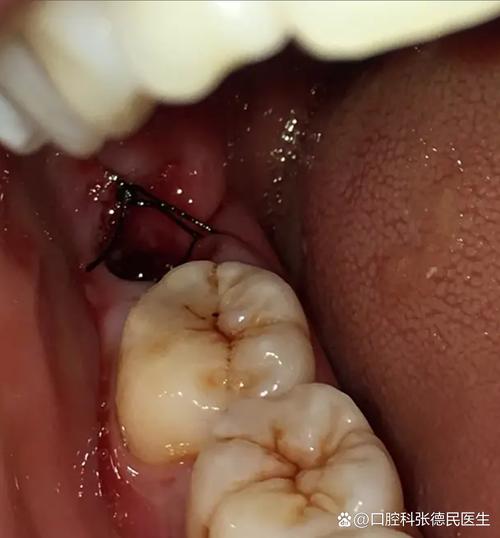

孕期雌激素和孕激素水平显著升高,会改变牙龈对局部刺激的反应性,易引发“妊娠期龈炎”,若种植体周围存在食物嵌塞、菌斑堆积,或口腔卫生维护不当,可能进一步发展为“种植体周围炎”,表现为种植体牙龈红肿、出血、溢脓,甚至导致牙槽骨吸收,影响骨结合效果,临床数据显示,妊娠期龈炎的发生率可高达50%-70%,而种植体周围软组织对炎症的抵抗力较天然牙更弱,需格外警惕。

- 告知医生妊娠情况:尽快联系种植牙医生,明确怀孕时间(孕周)、是否为高危妊娠(如先兆流产、妊娠期高血压等),医生会通过临床检查(探诊、叩诊)及影像学评估(孕期尽量避免X光,必要时可做CBCT,需铅衣防护)判断种植体稳定性及周围组织健康状态。